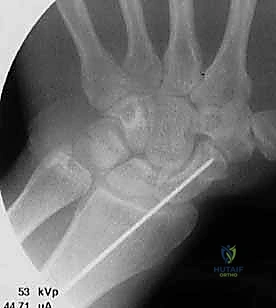

تقنية "التثبيت عن طريق الجلد" (Percutaneous Fixation) هي إجراء جراحي طفيف التوغل (Minimally Invasive). بدلاً من فتح الرسغ، يقوم الجراح بإجراء ثقب صغير جداً في الجلد (لا يتجاوز 3-5 مليمترات). من خلال هذا الثقب، وباستخدام جهاز الأشعة السينية المباشر في غرفة العمليات (C-arm Fluoroscopy)، يتم إدخال سلك توجيهي دقيق، ثم يتم إدخال مسمار خاص يسمى "مسمار ضغط بدون رأس" (Headless Compression Screw) مثل مسمار هيربرت (Herbert Screw).

هذا المسمار العبقري يتم دفنه بالكامل داخل العظم (تحت سطح الغضروف حتى لا يحتك بالمفاصل الأخرى)، ويتميز بوجود أسنان لولبية (Threads) في طرفيه بمسافات مختلفة. هذا التصميم يجعله يسحب طرفي الكسر ويضغطهما معاً بقوة هائلة (Compression)، مما يحفز التئام العظم بسرعة فائقة ويمنع أي حركة بين طرفي الكسر.